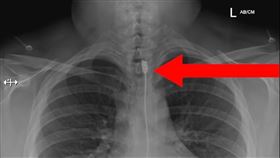

女喘不過氣送醫 照X光驚見充電線卡體內

波蘭一名女子因呼吸困難緊急送醫,沒想到,醫生照X光檢...

2022/11/16 21:32